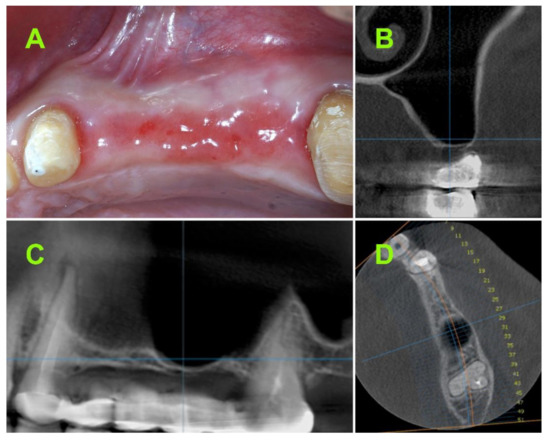

2. Materials and Methods

2.2.1. Pre-Operative CBCT Measurements

2.2.2. Surgical Techniques

2.2.5. Bone Height Evaluation of Newly Regenerated Bone

2.2.6. Evaluation of 1-Year Bone Remodelling